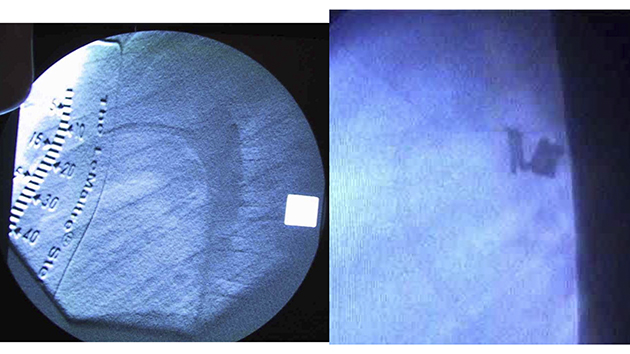

PDA closing coils. At the beginning, we mainly used 0.052 inch coils, while optionally used Flipper coils.

The 6th case of all caths, while 5th cath as the transcatheter closure of PDA at the first visit. 1 year 7 months girl with body weight of 10kg. Her PDA was closed using two 0.052 inch coils, 8mm/8cm and 6mm/8cm.